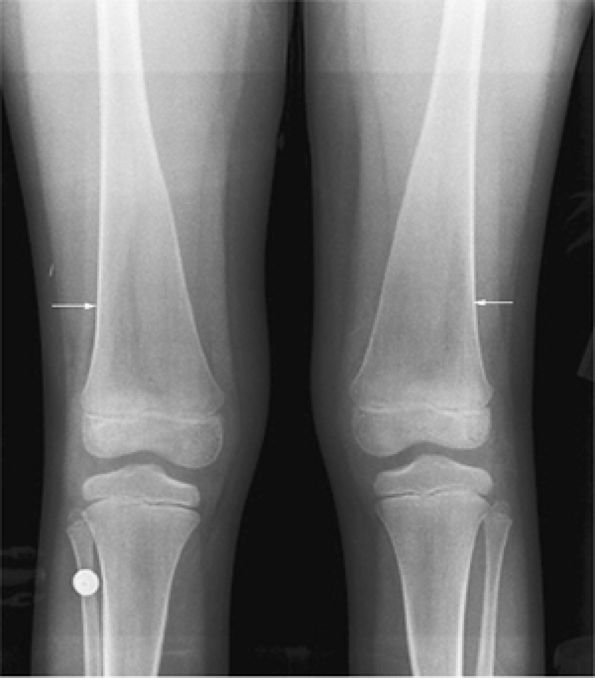

FIGURE 13.76 ● Undertubulation of the distal femurs causes characteristic Erlenmeyer flask deformity (arrows), as shown on an anteroposterior radiograph of the knees.